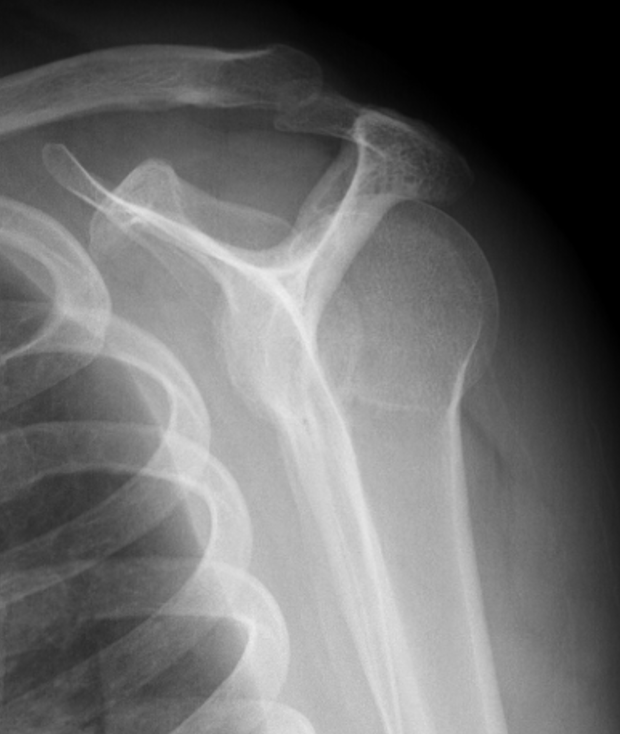

AP Xray

Abnormal overlap of humeral head on glenoid

Light-bulb sign - globular head secondary to internal rotation of the humeral head

Vacant Glenoid Cavity - > 6 mm space between humeral head and anterior rim of glenoid